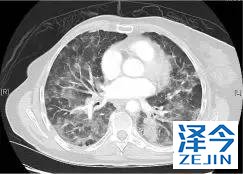

一位77岁的女性患有EPS15-NTRK1 IV期非小细胞肺癌,我们可以看到她的双肺满是病灶,并且出现了肝脏和脑转移,可以说是非常非常晚期了,

肺靶病变达到缓解,我们可以明显的看到前后的图像,病灶明显缩小了,

脑转移病变显示缩小了95%!

初始, 2018年6月 3周期 2018年8月